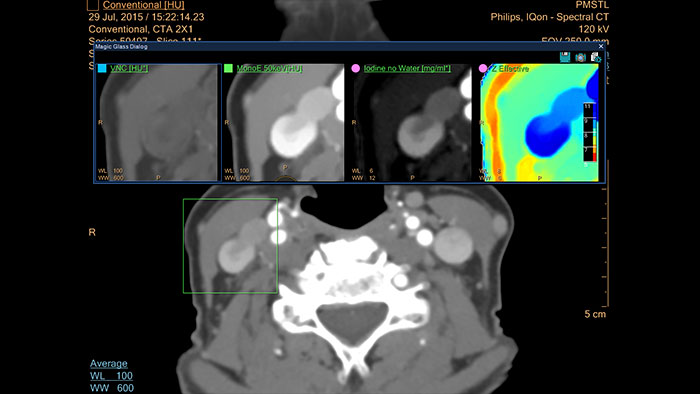

Spectral Light Magic Glass

CT Spectral Light Magic Glass

Review spectral data in a range of not spectral-enhanced CT applications

Allows retrospective use of spectral data that was saved in a series of spectral base images (SBI).

The fast launch of LMG allows review and identification of the most relevant results to be launched into the application for further analysis.

Spectral Magic Glass on PACS

CT Spectral Magic Glass on PACS*

IQon Spectral CT Functionality

IQon Spectral CT is the only scanner to offer CT Spectral Light Magic Glass and CT Spectral Magic Glass on PACS, helping radiologists review and analyze multiple layers of spectral data at once, including on their PACS.

• On-demand simultaneous analysis of multiple spectral results for an Region Of Interest (ROI).

• Integrates into a health system’s current PACS setup for certain PACS vendors.

• Spectral results viewable, during a routine reading.

• Enterprise-wide spectral viewing and analysis allows access to capabilities virtually anywhere in the organization.